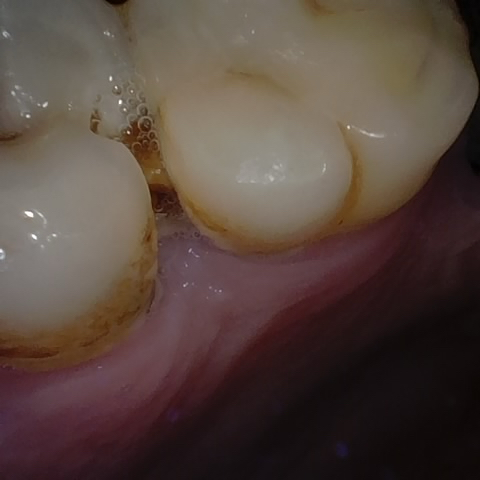

Annotated as "Good"